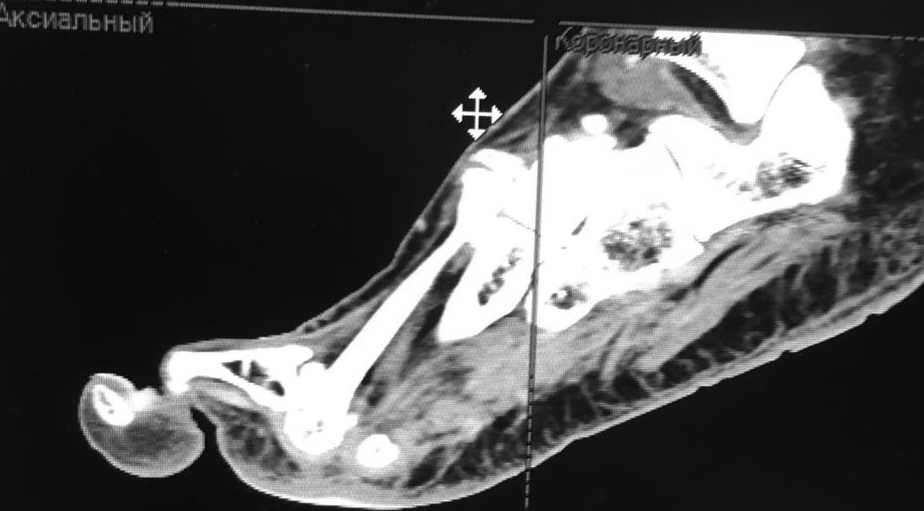

женщина средних лет, оперирована около года назад

заранее извиняюсь за скудность информации (консультация заочная). Насколько я понял, беспокоит метатарсалгия. Достаточно будет укоротить II-IV? Что-то другое? на что обратить внимание?

Судя по снимкам - болезнь Фрайберга по II лучу. Открытая моделирующая остеотомия головки II плюсневой и основания проксимальной фаланги II пальца, Weil с поднятие головки, III-IV лучи малоинвазивно.

Неутолимое желание поставить больше железок. 6 или 7 винтов и 2 пластины на одну плюсневую. Первичных снимков нет, но можно предположить, что 2 остеотомии привели к значительному укорочению М1. В результате - переходная метатарзалгия. Была или нет до операции деформация центральных пальцев тоже не знаем. Сейчас видны молоткообразная деформация второго пальца с преобладанием его длины над первым, перекрест второго и третьего пальцев. Если выпрямить второй - станет еще длиннее. А выпрямить может помешать отклоненный кнутри третий палец - второму некуда улечься. Поэтому нужно думать об остеотомии 2-4 плюсневых для устранения метатарзалгии (фиксированный или нефиксированный Вейль, DMMO - чем владеете), коррекции молоткообразной деформации второго (с его укорочением) и варусной деформации третьего пальца (возможно и четвертого, если будет мешать выпрямить третий). На болезнь Фрайберга не очень похоже. Скорее это подвывих пальца на некачественных снимках имитирует. В любом случае - моделирующая резекция - калечащая сустав операция. Декомпрессии за счет укорочения будет достаточно. Если есть возможность оперировать чрескожно - самый простой и беспроигрышный вариант.

Подвывих по 2-му лучу - большой. Может дополнительно подумать об удлинении разгибателей.